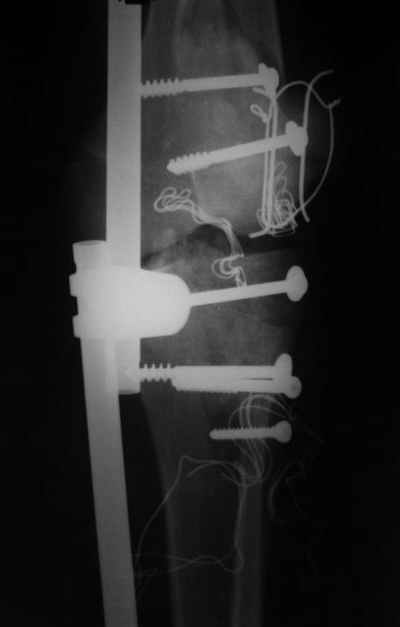

ET> насколько целесообразно в данном случае наложение spanning ex fix

ET> после обработки и фиксации переломов.

Можно наложить два гибридных аппарата на оба смежных суставных конца, возможно, в сочетании с минимальной внутренней фиксацией компрессирующими винтами, и временно аппараты соединить.

Тогда по паре стержней в диафиps бедра и tibia, и этот самый spanning fixator.

№4 снимок через два дня после операции, супракондилярный перелом, при поступлении конечность была холодная и без пульса, подозрение на повреждение сосудов, сделана ABI (ankle-brachial index) в приемном отделении, индекс меньше 1 к 0.9 в норме 1 к 1.1, срочная ангиография в операционной после Ex-Fix, по два стержня в сегменте наложен в течение 20 мин, повреждение подколенной артерии, ушивание сосудистым хирургом через медиальный доступ в дистальном отделе бедра и двухразрезная профилактическая фацсиотомия, перкутанная фиксация каннюлированными шурупами несмещенного перелома шейки бедра и дополнительные стержни в фиксаторе для жесткости.